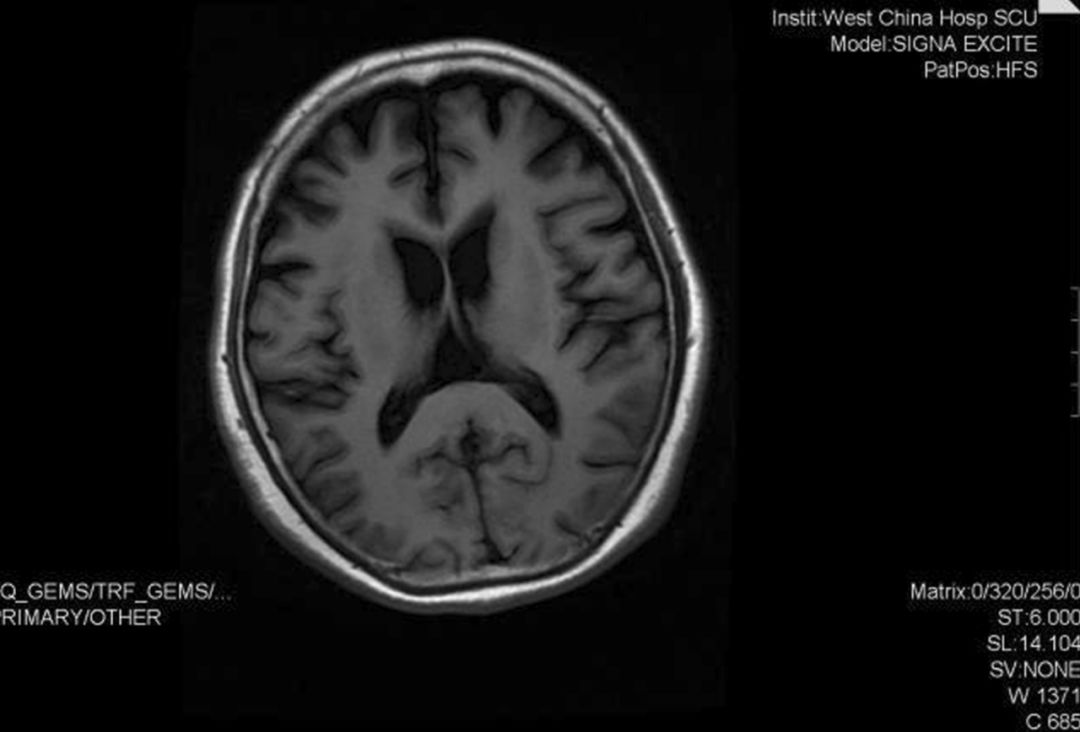

图2 2018年9月头部MRI示轻度额颞叶萎缩(Li X, et al. 2020)

住院期间,患者头部MRI显示轻度额颞叶萎缩(图2)。MMSE得分为16/30(满分30分),表现出短暂的方向感丧失、注意力、计算能力和语言能力方面的缺陷,以及记忆延迟。MoCA得分为9/30(满分30分),结果提示患者在视觉空间组织、注意力、语言能力、时间取向和抽象思维方面存在缺陷。日常生活活动量表(ADL)总分为54分,提示日常生活活动困难。